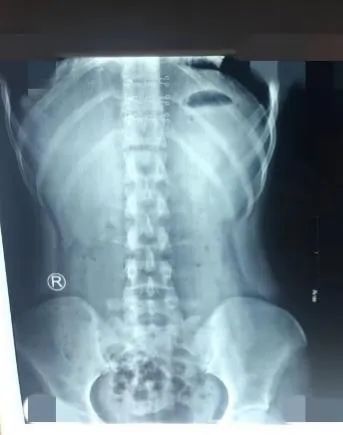

青少年患者治疗后

患者的脊柱侧弯度数得到改善